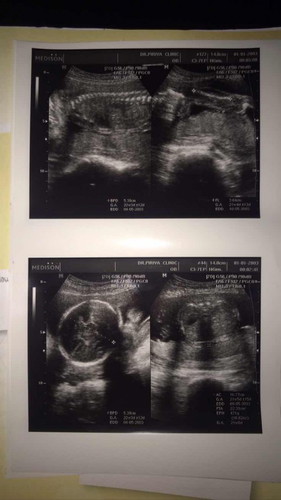

21 W 5 D ไม่เห็นเพศจ้า น้องหนีบไว้แน่นเลย คุณหมอบอกว่า น้ำหนักตัวน้อย 471 กรัมแล้ว แต่ในแอป 360 กรัม น้ำหนักอิแม่เองก็ขึ้น 3 โล 4 ภายใน 1 เดือน หมอสั่งให้ควบคุมน้ำหนัก และเดือนหน้านัดตรวจเบาหวาน. หน้านี้มะม่วงก็กำลังสุก ทุเรียนก็อร่อย ใครจะอดใจได้ละค้าาา #ทีมสิงหาคม #ใครมีประสบการณ์ คอมเม้นมาคุยกันค้า